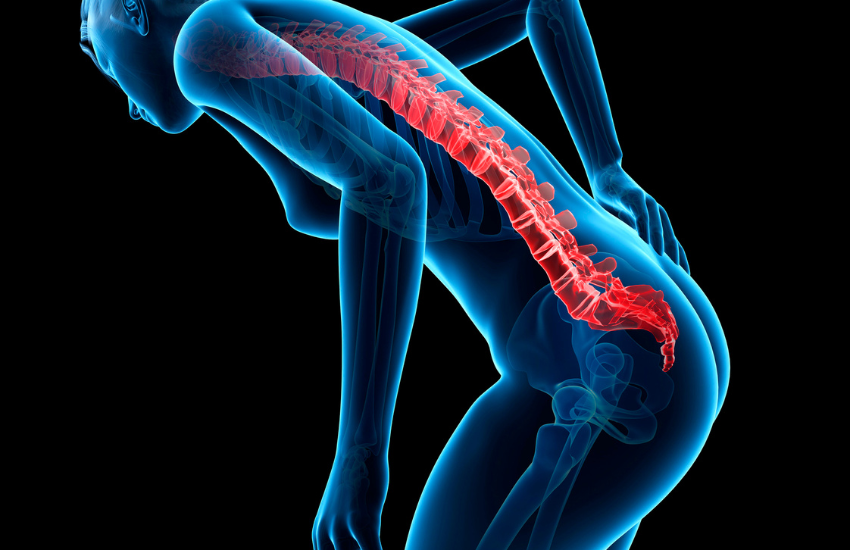

Na maioria das situações, a lombalgia ou dor lombar, resulta de uma patologia da coluna vertebral, frequentemente de natureza degenerativa, mas pode também ser postural ou devida a esforço, a acidente, a fenómenos inflamatórios ou ainda a problemas relacionados com os discos intervertebrais (ruptura ou hérnia).

A região lombar é essencial para a coluna vertebral, pois é o principal ponto de apoio do tronco. Além disso, ela é constituída por 5 vértebras, ligamentos, músculos e discos invertebrados e é responsável por sustentar grande parte do peso corporal bem como ajudar a movimentar o corpo.

Este termo refere-se à presença de dor na região da coluna lombar, geralmente entre as últimas costelas e acima dos glúteos, que algumas vezes pode irradiar para os membros inferiores com ou sem dormência. É, portanto, um sintoma bastante comum e incapacitante e não uma doença, o que significa que se pode manifestar na presença de diversos quadros clínicos.